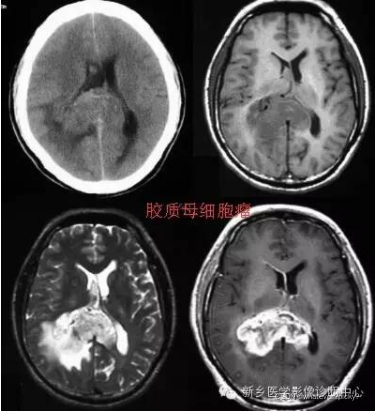

高级别(间变性星形细胞瘤和多形性胶质母细胞瘤)胶质瘤 (HGG) 和 低级别胶质瘤 (LGG) MRI(组织学诊断:星形细胞瘤或少突星形细胞瘤)组成。

本文介绍了脑部MRI图像在胶质瘤级别分类中的作用,包括高级别和低级别胶质瘤的特点,以及它们的治疗和预后。胶质瘤的病理级别直接影响治疗方案和预后,而现代影像学技术能够帮助医生在术前准确评估肿瘤的恶性程度。手术是主要治疗手段,结合放疗和化疗可提高疗效。